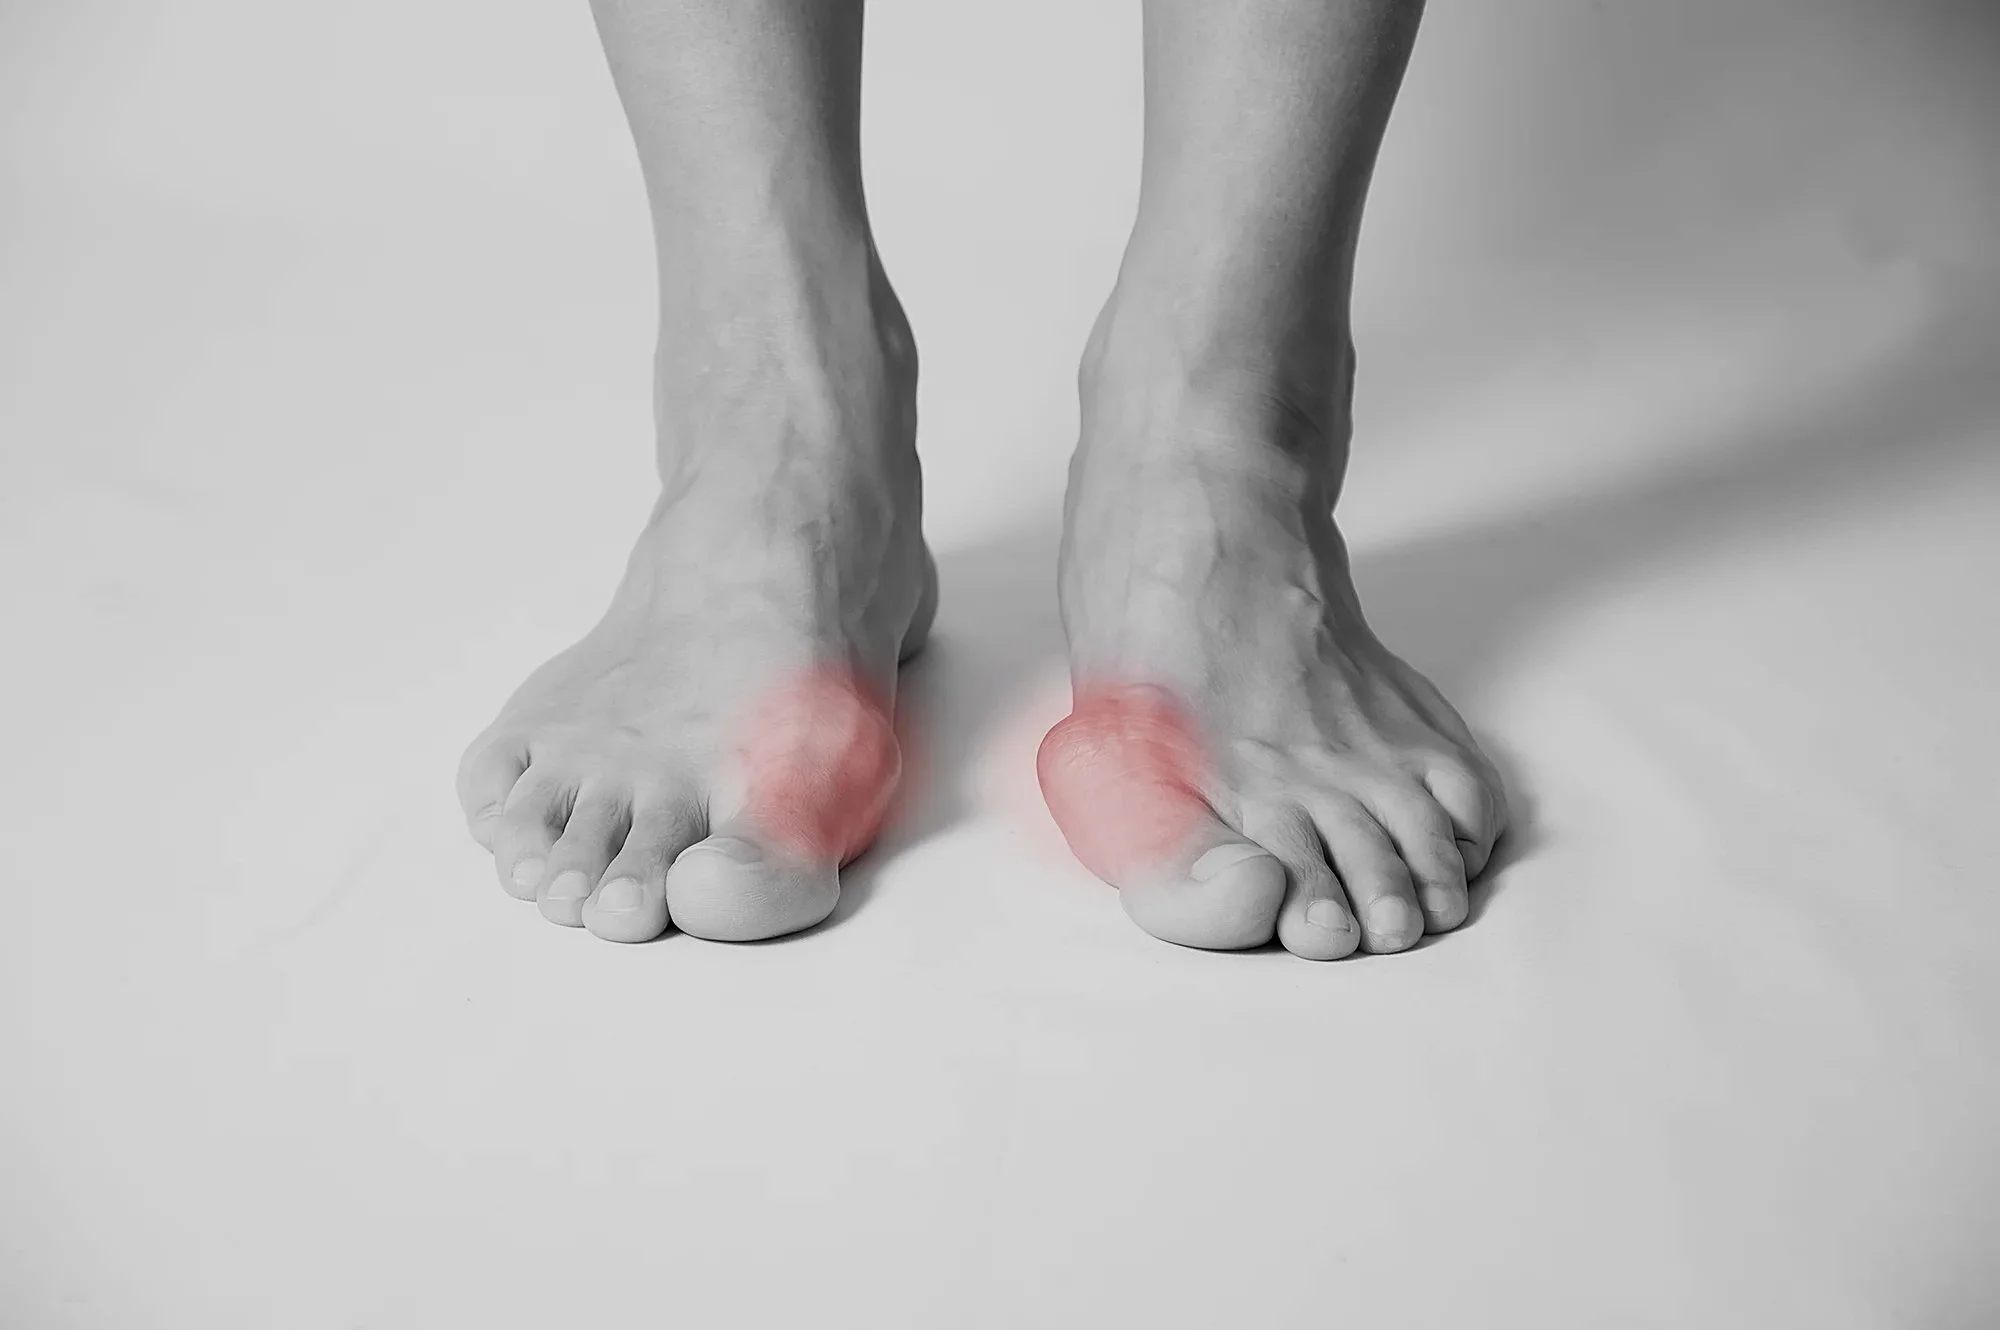

You have developed arthritis of the big toe joint. This is often associated with a bony bump(s) on the side or top of the joint. This bump may have become red and sore and is often called a 'Bunion'.

Arthritis of the big toe joint is fairly common in people over 50. Wearing shoes that are too tight or being flat-footed may also contribute to the formation of a bunion/arthritic joint.